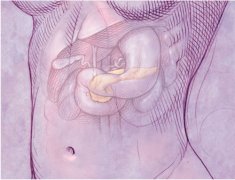

十二指腸炎是指發(fā)生于十二指腸的炎癥,分為原發(fā)性和繼發(fā)性兩種,原發(fā)性者也稱非特異性十二指腸炎。本病臨床癥狀缺乏特征性,主要表現(xiàn)為上腹部疼痛、惡心、嘔吐、嘔血和黑便,有時(shí)和十...

十二指腸潰瘍是一種很常見的消化疾病,一擔(dān)患上患者要積極的治療這種病,這種病的出現(xiàn)會(huì)給患者帶來極大的麻煩,除了吃藥抑制以外,最主要的治療手段還是通過手術(shù)來根治。那么,十二指...